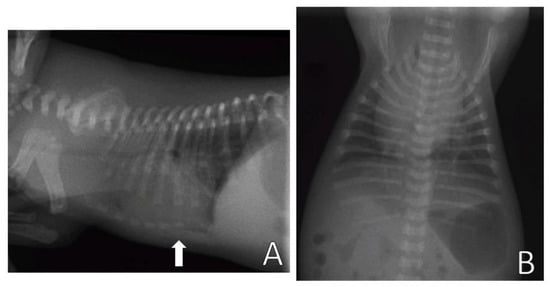

The evaluation of pectus excavatum can be performed by measuring the frontosagittal and vertebral indices (Figure 1) on chest X-rays [15,16,19]. Table 1 shows the normal thoracic indices in dogs of nonbrachycephalic breeds, brachycephalic breeds and cats. Based on these indices, pectus excavatum can be classified as mild, moderate or severe [15,16,19] (Table 2). Figure 2 shows radiographs of neonatal puppies of brachycephalic breeds with normal thoraxes and with different degrees of pectus excavatum.

Figure 2.

Chest X-rays of neonatal puppies of brachycephalic breeds. (A) Chest without alterations, indices—frontosagittal: 1.14 cm; vertebral: 13.4 cm. (B) Pectus excavatum of mild degree (arrow), indices—frontosagittal: 2 cm; vertebral: 11.25 cm. (C) Pectus excavatum of moderate degree (arrow), indices—frontosagittal: 3 cm; vertebral: 6 cm. (D) Severe pectus excavatum (arrow), indices—frontosagittal: 3.14 cm; vertebral: 5.8 cm.